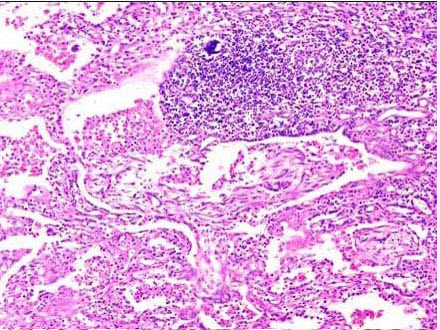

肺气肿,这个听起来有些遥远的病症,却悄然无声地侵蚀着我的呼吸。它的症状不仅仅是大声的咳嗽和喘息,更是日常生活中无处不在的限制。我开始意识到,即使是简单的家务活,也会让我喘不过气来。每一次深呼吸,都像是在和自己的身体做斗争。

医生告诉我,肺气肿是慢性阻塞性肺疾病的一种,吸烟是主要的诱因之一。我回想起自己年轻时的烟瘾,不禁感到后悔。但后悔无用,现在最重要的是学会与这个病症共存。我开始学习各种呼吸练习,尝试改善生活习惯,希望能缓解症状。